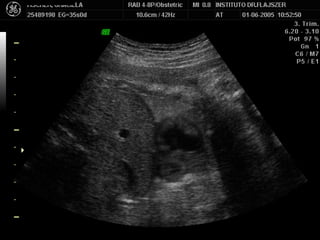

Ubicación